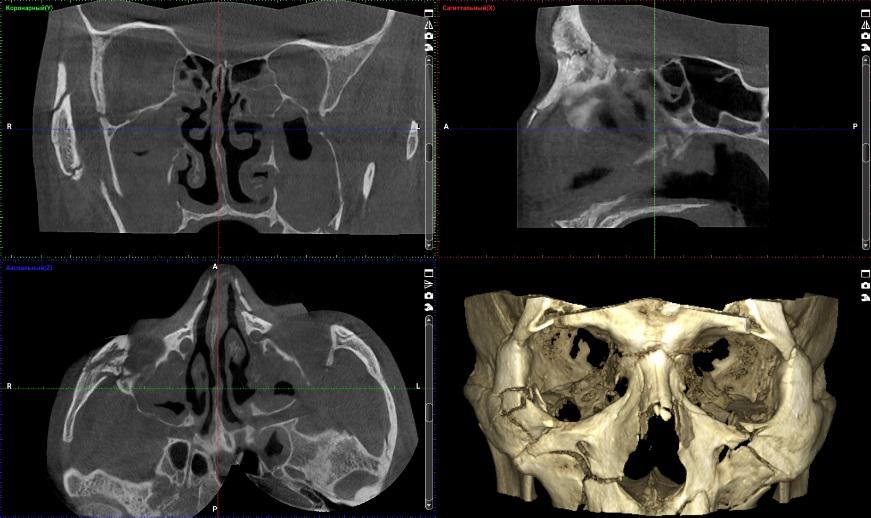

Дентальна комп’ютерна томографія (КТ) — це діагностична процедура в сучасній стоматології. Її результат дозволяє терапевту достовірно оцінити стан та анатомічні особливості кореневих каналів, локалізувати запальний процес. Ортопед може побачити точне розташування, будову СНЩС, імплантолог — оцінити параметри щелепної кістки, структуру, щільність та об’єм.

3D знімок — точний метод діагностики, лікар отримує повну інформацію про стан щелепно-лицьового апарату пацієнта, гайморових пазух. Отримані в результаті сканування знімки дають можливість стоматологу збільшувати, повертати і досліджувати під кутом області, що цікавлять, що неможливо при рентген-дослідженні. Також комп’ютерна томографія вимірює висоту, ширину кістки, визначає тип. Це потрібно, щоб підібрати розмір та тип імплантату при плануванні операції.

• патології нижньощелепного суглоба;

• виявити запалення у гайморових пазухах та слізних каналах, які можуть стати тимчасовою перешкодою до імплантації;

• уточнити анатомічну будову верхньощелепних синусів, нижньощелепного каналу та інших кісткових структур, щоб спланувати кут нахилу при встановленні штучного стрижня;

• виявити аномалії зубощелепної системи, патології скронево-щелепного суглоба для правильного моделювання ортопедичної конструкції на імплантат;